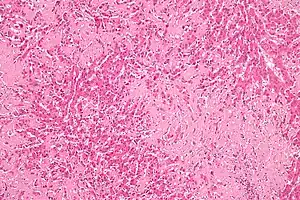

| Micrograph of liver amyloidosis, H&E stain |